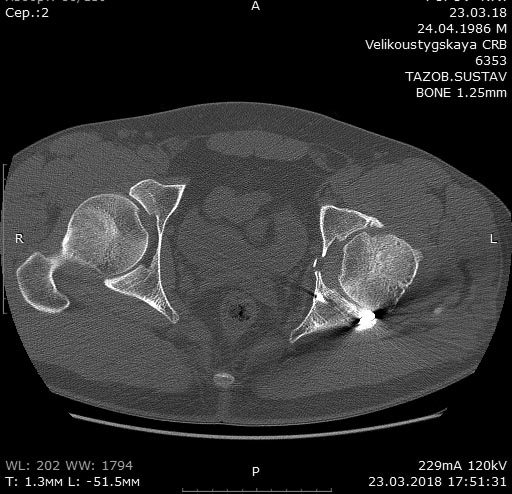

Мужчина 32 года, беспокоят боли в левом тазобедренном суставе, преимущественно в задних отделах при отведении ноги, иногда боли в паху с иррадиацией по внутренней поверхности до колена.

Травма в 2015 году. Водитель, попал в ДТП. Первично повреждение печени, перелом локтевой кости слева. Перелом задней колонный и задней стены левой вертлужной впадины. По экстренным показаниям выполнялась лапаротомия. Синтез задней колонны и задней стены через 13 дней через доступ Кохера-Лангенбека. Гладкий послеоперационный период. Выписан на амбулаторное лечение через 15 дней после операции. После выписки к нам не обращался, так как является жителем другого региона. Обратился через 2,5 года с жалобами на боли в области левого тазобедренного сустава.

На РКТ таза - перелом сросся. Отмечается кисты в области верхнего полюса головки бедра. Пластина фиксирующая задний край соприкасается с задними отделами головки бедра (видимо произошел частичный лизис костного края).